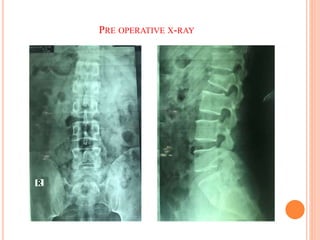

PRE OPERATIVE X-RAY